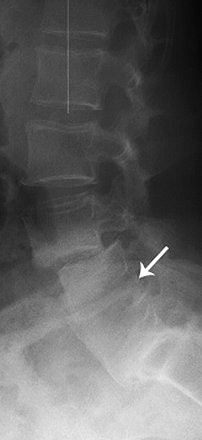

| Lateral radiograph shows partial fusion. Krestan CR, Helge H, Vasilevska V, Weber M, Schueller G, Imhof H , and Czerny C, "MDCT Versus Digital Radiography in the Evaluation of Bone Healing in Orthopedic Patients" (AJR 2006; 186:1754-1760). |

Overall agreement between the two modalities was found in 63% of the patients. Digital x-ray overestimated the bone healing process in 19% of the patients and underestimated it in 19% as well.